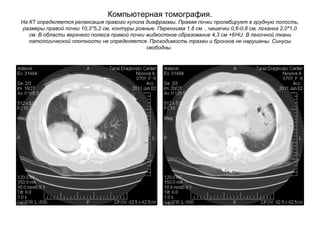

Компьютерная томография.

На КТ определяется релаксация правого купола диафрагмы. Правая почки пролабирует в грудную полость,

размеры правой почки 10,3*5,2 см, контуры ровные. Паренхима 1,8 см. , чашечки 0,6-0,8 см, лоханка 2,0*1,0

см. В области верхнего полюса правой почки жидкостное образование 4,3 см +6HU. В легочной ткани

патологической плотности не определяется. Проходимость трахеи и бронхов не нарушены. Синусы

свободны.